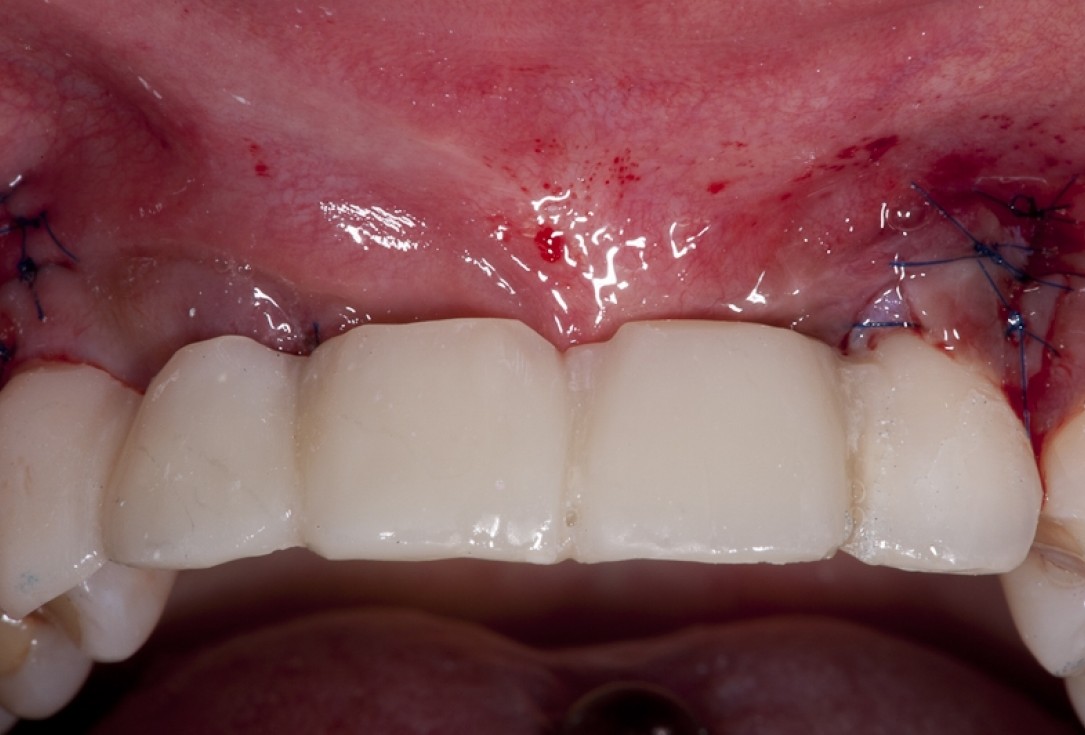

15/17 - Situation after sutures removal and healing period of two weeks

Block augmentation with maxgraft® block & mucoderm® - Dr. K. Chmielewski